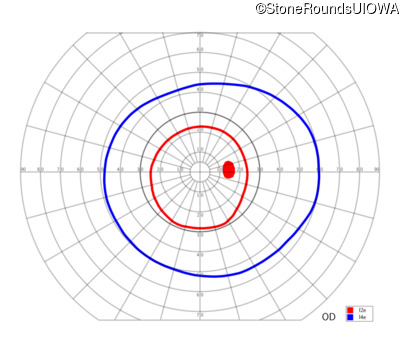

| Age at visit: 6 years |

| Age at visit: 11 years |

| Age at visit: 14 years |

| Age at visit: 14 years (Visit 2) |